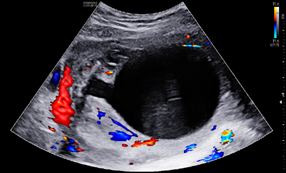

A 25-year-old G2P1001 at 19w2d presented for anatomic ultrasound. Routine prenatal genetic screening indicated an elevated risk for Down syndrome, 1:259. Her prenatal course was otherwise uncomplicated. Initial anatomical evaluation noted adequate amniotic fluid, a markedly distended fetal urinary bladder, moderate-to-marked bilateral renal hydronephrosis, a moderate degree of bilateral hydroureter, and bilateral renal cortical cysts, (Figures 1-4). Patient was sent for second opinion with secondary survey, within 1 week, denoting bladder outlet syndrome with oligohydramnios. A characteristic "keyhole" sign was noted (Figure 5). Patient initially elected for genetic non-invasive prenatal testing and later for genetic amniocentesis, the results of which revealed a normal karyotype/FISH/microarray. At the time of amniocentesis, bladder tap was performed and yielded 160cc of fluid for evaluation of renal function based on urine sodium, chloride, urine osmolality and calcium levels. At 22w3d patient presented for follow up sonographic evaluation; findings revealed significant fetal abdominal ascites, persistent oligohydramnios, a "bell-shaped" chest with only the left lung measurable, and the right lung poorly defined. Bilateral urinary tract dilation was again observed, with the right kidney measuring 2.0 x 3.0cm and the left kidney measuring 2.3 x 1.7cm. The kidneys were echogenic in nature and the parenchyma was thickened up to 7mm, with no pyramids visible. The bladder had severe thickening, measuring up to 7.7mm in diameter. The bladder measured 4.7 x 1.7cm with intraluminal calcifications noted both in the bladder and intestines. The patient was counseled on these new findings and concern for both pulmonary hypoplasia and possible poor renal function. The patient was given the option to proceed with fetal urinary evaluation for renal function and possible bladder shunt vs termination of pregnancy secondary to these findings; she elected for pregnancy termination.1–3

Figure 1 Distended fetal urinary bladder.

The presence of a posterior urethral valve prevents normal fetal micturition, resulting in bladder distension and subsequent distension of the ureters and kidneys. Diagnostic features of posterior urethral valves on sonography varies, but classically presents in male fetuses with fetal megacystis that may fill the entire abdomen, thickened bladder wall (>3mm) with prominent trabeculae, oligohydramnios, and bilateral hydronephrosis with hypoechoic renal parenchyma and/or cortical cysts that can indicate renal dysplasia. The best diagnostic clue is the presence of a dilated posterior urethra (“keyhole” sign) . While not always seen, its presence, suggests the diagnosis of PUV. These findings however, may be found in other urinary tract conditions. Megacystis is defined as a longitudinal bladder diameter (LBD) > 7mm in the first trimester. However, after the first trimester, it is most commonly defined as failure of bladder emptying during a 45min period of ultrasound examination.5